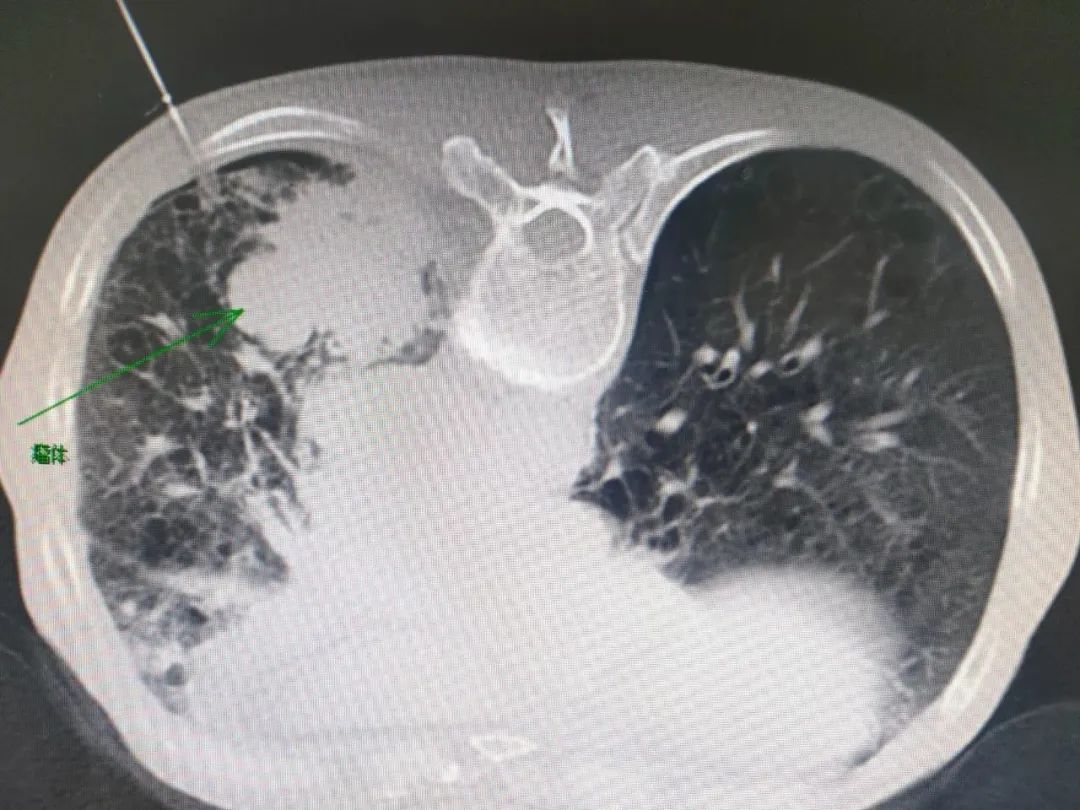

鉴于患者病情紧急,立即给患者行左侧“猪尾巴管”微创胸腔闭式引流术,术后引流出约1100ml黄色浑浊液体后,患者自觉胸闷、气短及恶心不适较前明显减轻,后期行胸部增强CT检查发现患者左肺下叶肺Ca伴阻塞性肺炎,左侧肺门、纵隔内及所扫肝门部、腹膜后多发淋巴结转移,左下肺静脉受侵,左侧胸腔积液;双肺肺气肿伴肺大泡形成,双肺间质纤维化改变。患者目前左肺占位考虑恶性可能性极大,在谢加利主任的主持下,科室进行讨论,患者左肺下叶占位考虑恶性可能性极大,瘤体靠近外周脊柱旁,建议穿刺活检。

当时患者手术有一定的难度和风险,双肺弥漫性肺气肿、肺大泡、肺间质纤维化,瘤体血供丰富,穿刺过程极易发生血气胸,同时患者下叶活动度大,穿刺成功几率低,CT引导下经皮穿刺活检对肺组织创伤小、定位准、并发症相对可控等。最后科室讨论一致决定行经皮肺穿刺活检术,在明确告知风险并经家属同意后,经过充分术前准备后,呼吸与危重症医学科团队和影像科团队密切配合,在谢加利主任指导下艾克东副主成功为患者实施了CT引导下经皮肺穿刺活检术。成功实施穿刺活检,术后病理回报:小细胞肺癌。